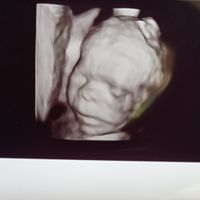

🍀🍀 creo in punta di piedi qst gruppo sperando che altre future pancine si aggiungano..🍀🍀incrocio le dita x tutte 🤞🏻🤞🏻forza.. forza 💪🏻💪🏻